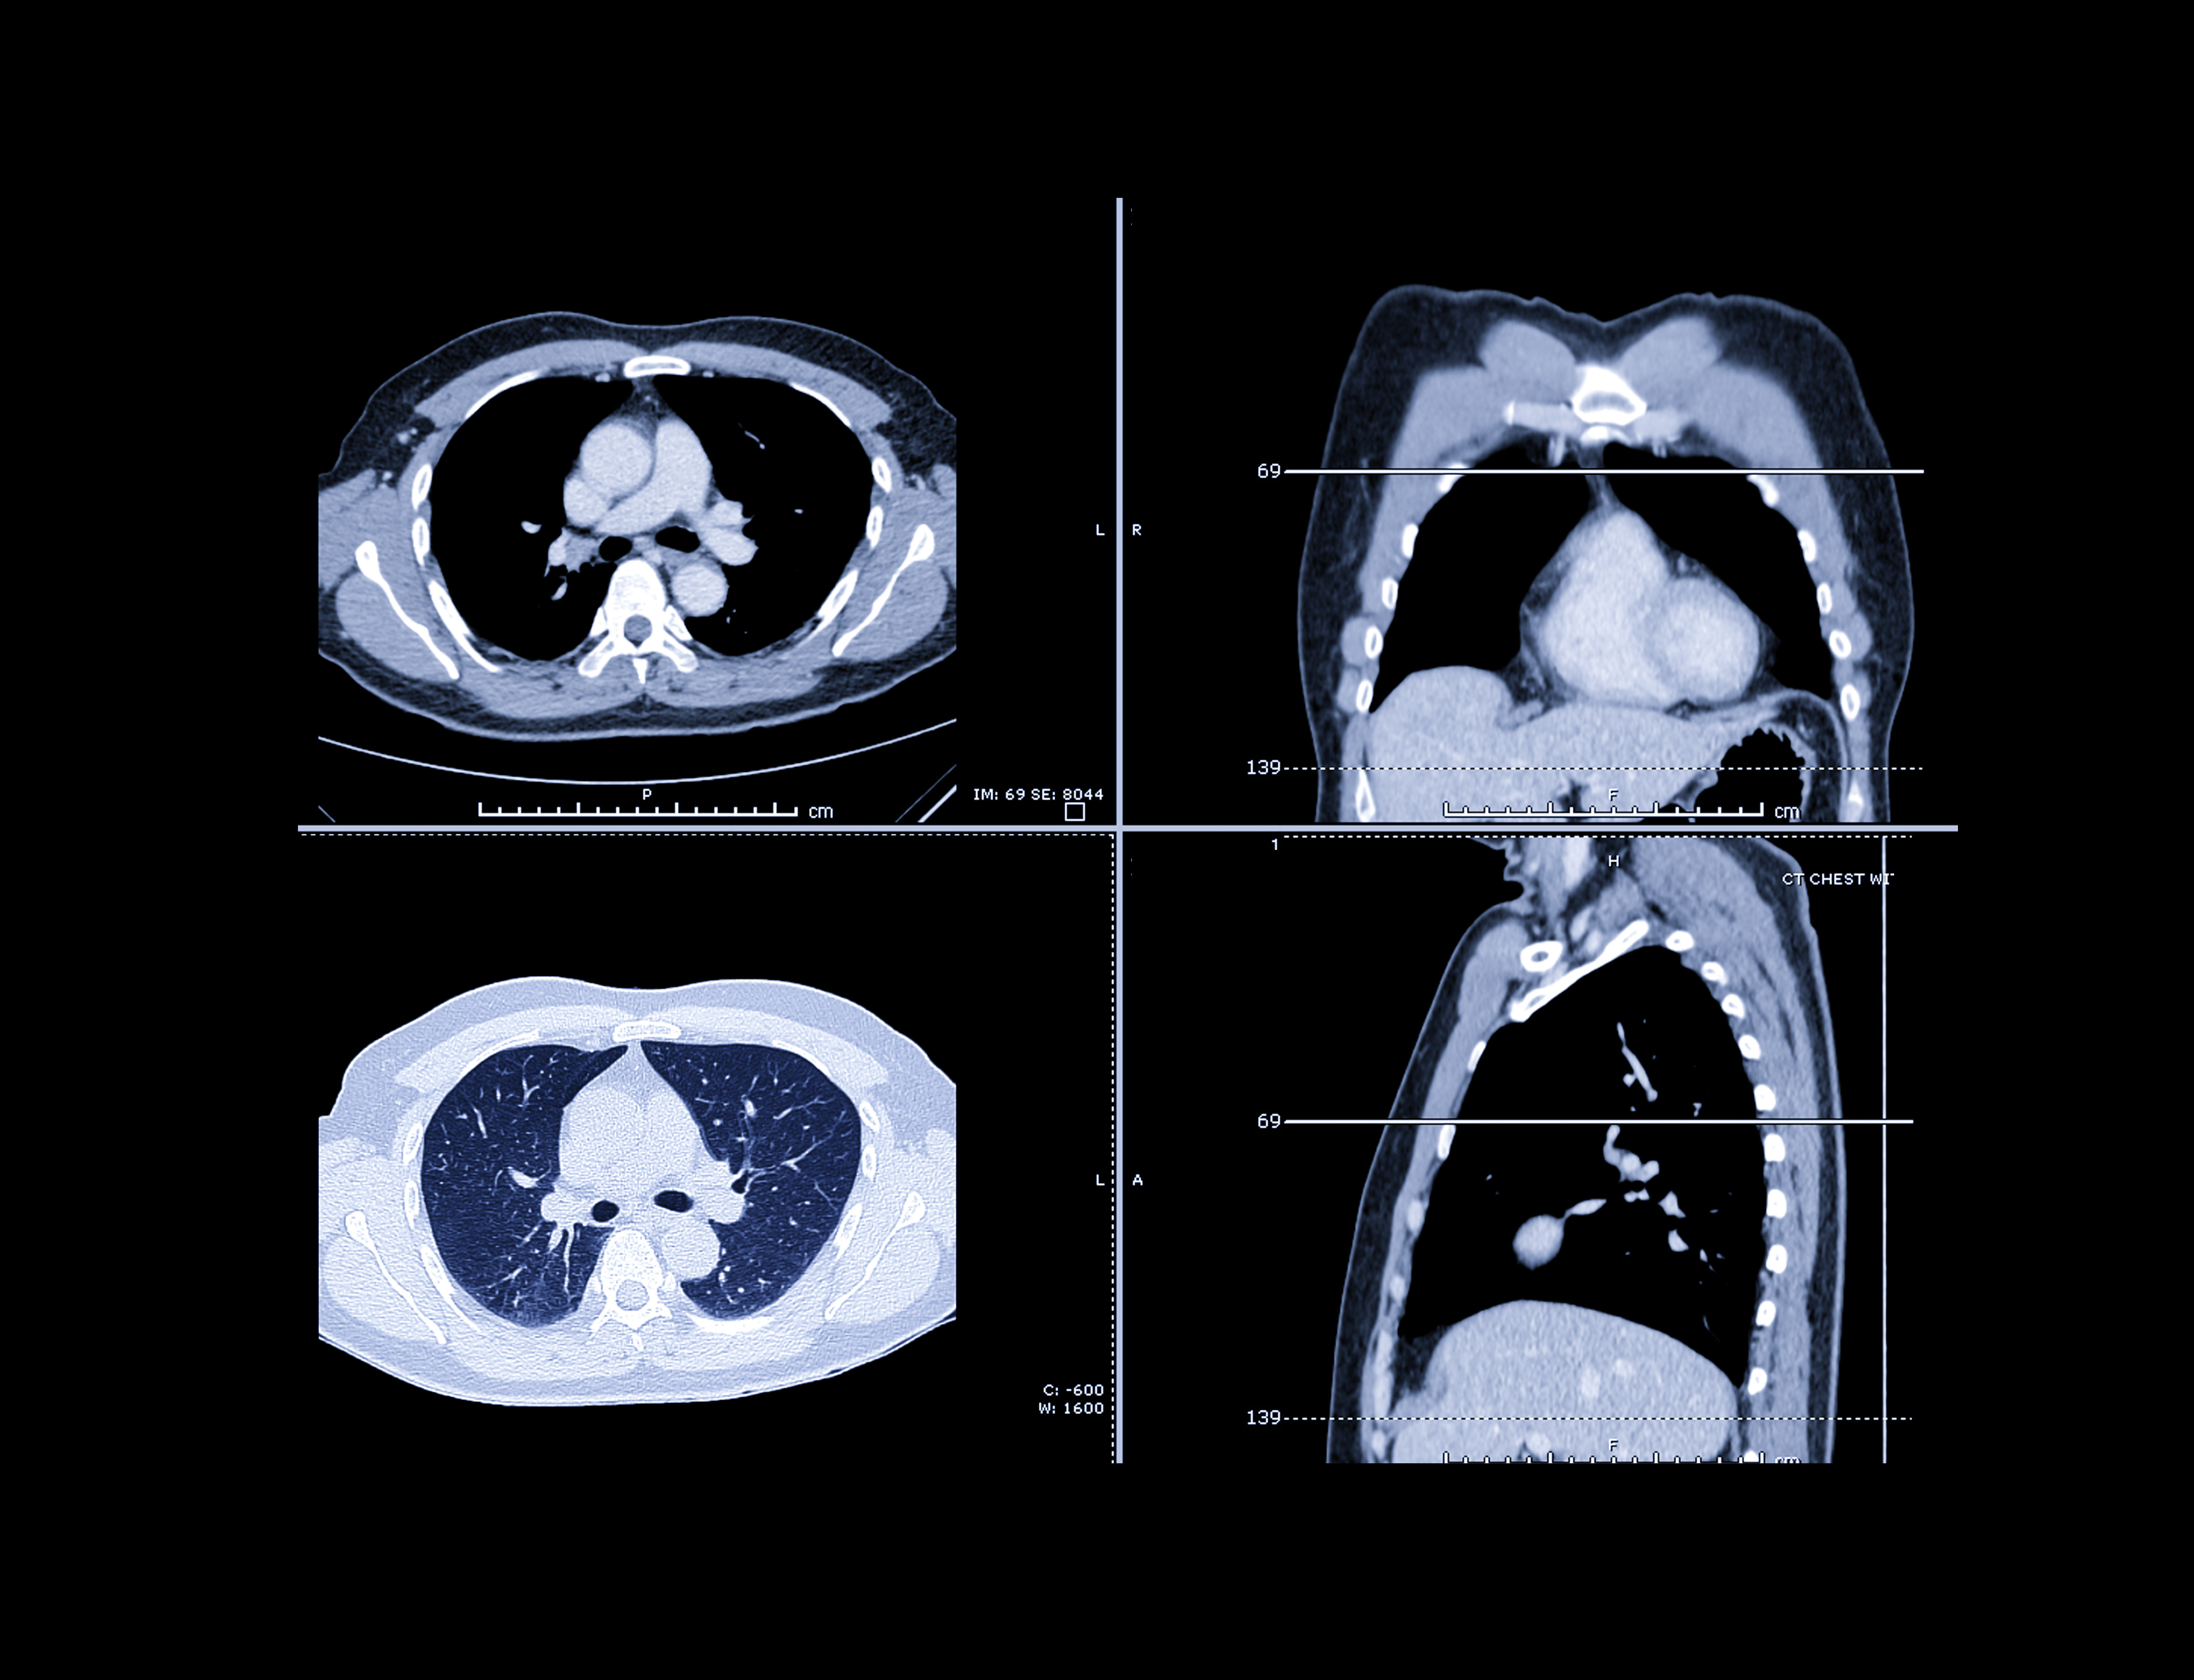

The companies are preparing to start clinical trials. Imidex's AI software VisiRad XR will be used to analyze chest x-rays and highlight possible lung nodules and masses. Orbit Genomics will then test those identified lung nodule patients with OrbiSeq-L, AI sequencing technology that provides highly specific insights about cancer from blood samples, Imidex said.

VisiRad XR was cleared by the U.S. Food and Drug Administration (FDA) in August 2023 and has demonstrated an 83% sensitivity in detecting lung nodules as small as 6mm, Imidex noted.